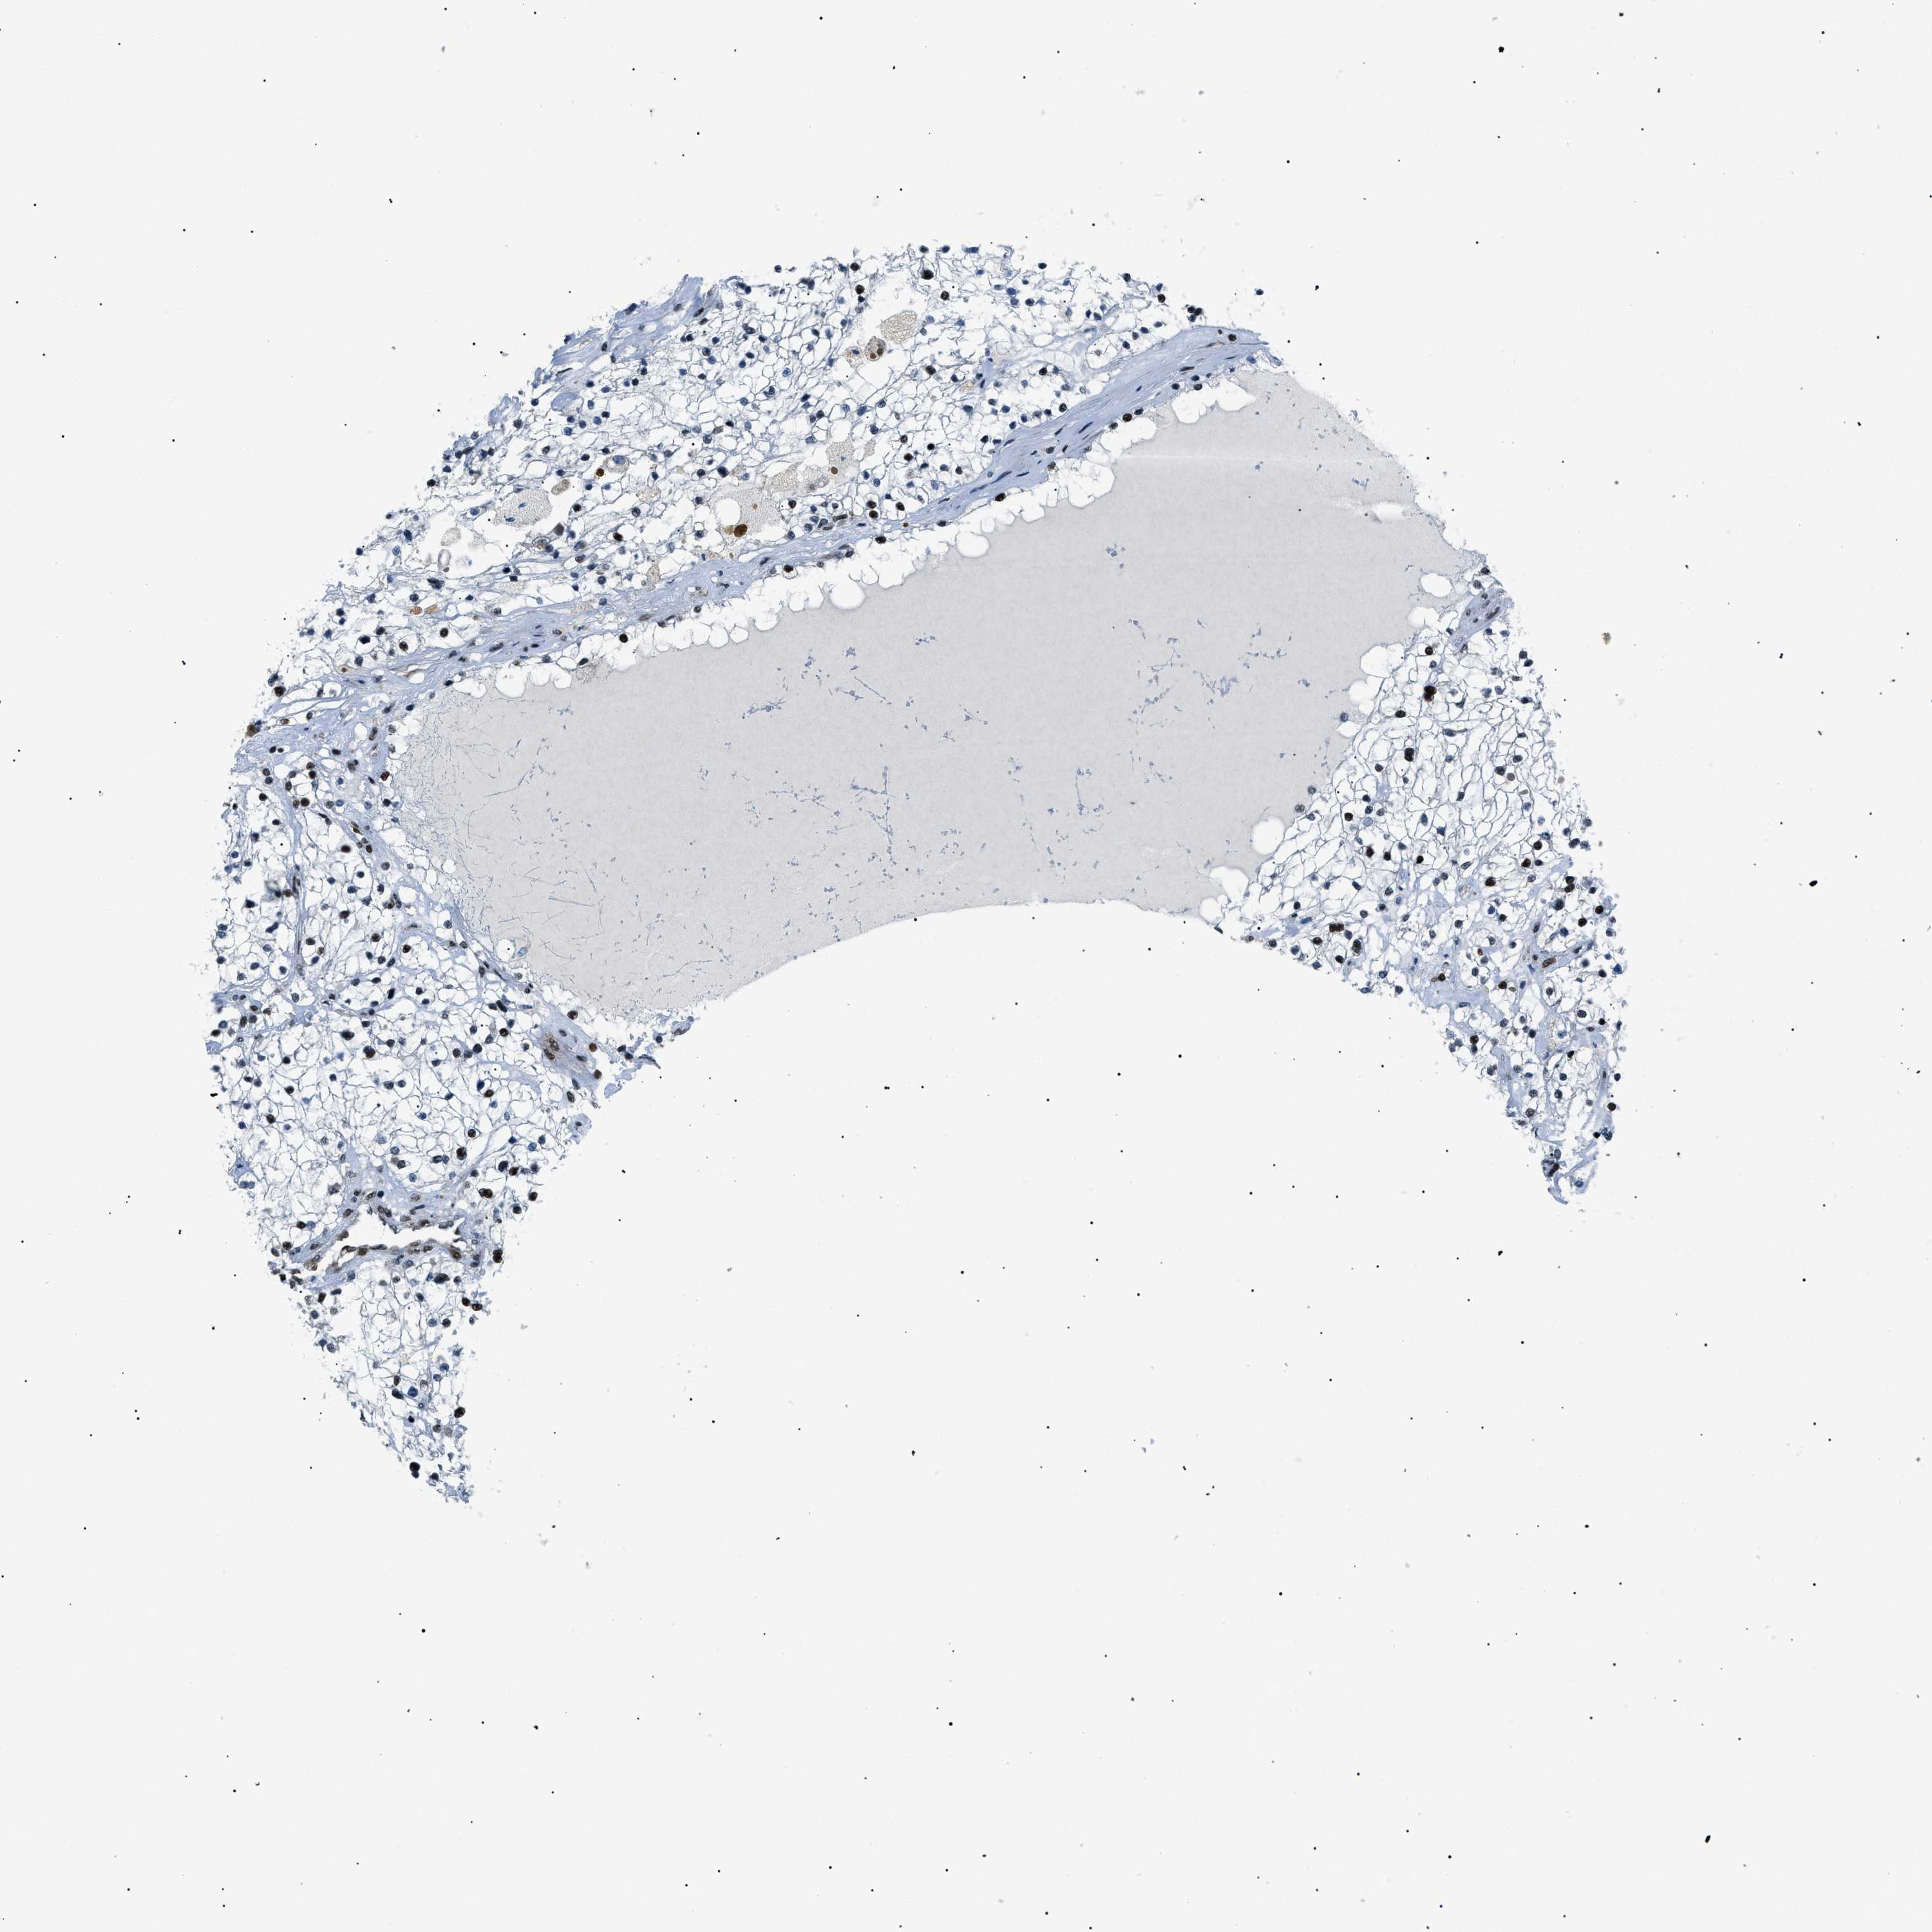

HNRNPK is validated prognostic, high expression is favorable in Kidney Renal Clear Cell Carcinoma (validation)

Best expression cut offi

Based on the FPKM value of each gene, patients were classified into two groups and association between prognosis (survival) and gene expression (FPKM) was examined. The best expression cut-off refers the FPKM value that yields maximal difference with regard to survival between the two groups at the lowest log-rank P-value. Best expression cut-off was selected based on survival analysis .

When clicking on this number, the vertical dashed line indicating cut-off, the interactive survival plot, and the Kaplan-Meier curve will be adjusted to show results based on the best expression cut-off.

: 384.93

TCGA RNA samplesi

RNA-seq data is reported as average FPKM (number Fragments Per Kilobase of exon per Million reads), generated by the The Cancer Genome Atlas (TCGA) .

Normal distribution across the dataset is visualized with box plots, shown as median and 25th and 75th percentiles. Points are displayed as outliers if they are above or below 1.5 times the interquartile range. FPKM values of the individual samples are presented next to the box plot.

Average pTPM 408.9

Number of samples 100